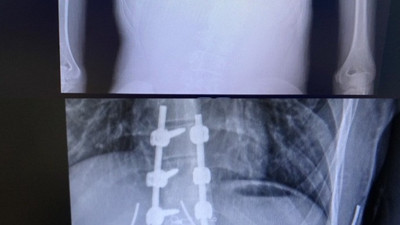

Doğuştan hasta genç kız ikinci ameliyatla sağlığına kavuştu. Mucize diye buna denir Diyarbakır’da doğuştan skolyoz hastası olan ve ilk ameliyat sonrası eğriliği artan 15 yaşındaki Hazal Oruç, Selahaddin Eyyubi Devlet Hastanesindeki başarılı geçen ikinci ameliyatla sağlığına kavuştuğu bildirildi.